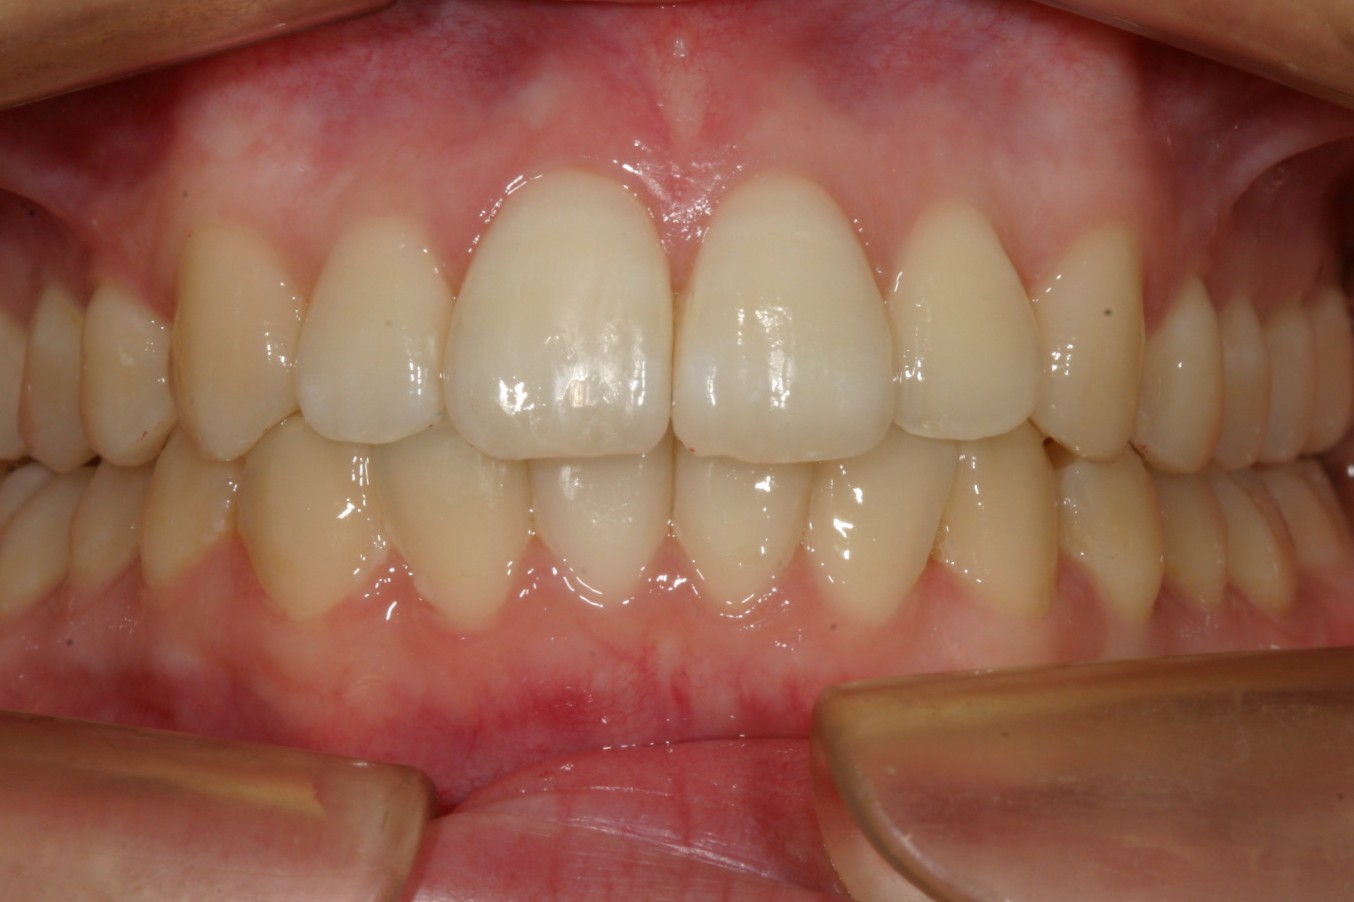

上顎のアーチをU字に変えて綺麗に配列しました。

下顎もU字に変えて配列しています。

前突も改善しました。